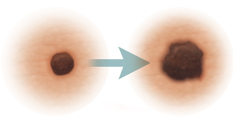

The first sign of melanoma is often a change in a mole, or the appearance of a new mole. These ABCDE rule can help you tell a normal mole from one that might be melanoma. The ABCDE rule is:

Asymmetry. One half of the mole does not match the other half.

Border irregularity. The edges of the mole are ragged or irregular.

Color. The mole has different colors in it. It may be tan, brown, black, red, or other colors. Or it may have areas that seem to have lost color.

Diameter. The mole is bigger than 6 millimeters across, about the size of a pencil eraser. But some melanomas can be smaller.

Evolving. A mole changes in size, shape, or color.